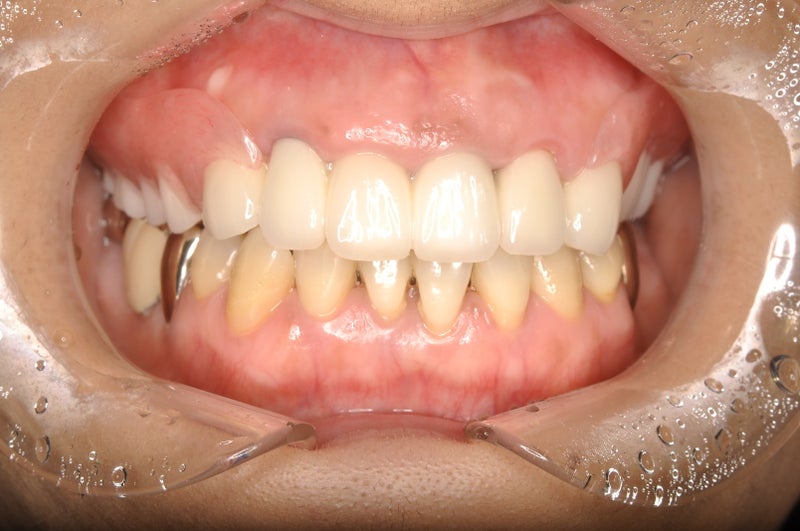

<after>

▶︎コストや、患者様のご希望を合わせた結果、インプラント治療は行わない方向で今回は治療を進めました。

現在はセラミックと歯のなじみも良く快適に生活を送っているようです。

ご本人も口の中への関心も高まり自主的に定期的にクリーニングやチェックに来ていただけるようになりました。🦷✨